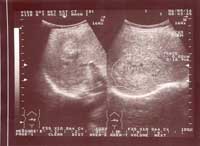

Một số hình ảnh siêu âm tổn thương gan do sán lá gan lớn:

Hình ảnh 1: Khối tổn thương gan do SLGL điển hình, Khối lớn với micro ap xe bên trong | Hình ảnh 2: Khối tổn thương gan do SLG điển hình: Khối lớn và có nhiều micro áp - xe bên trong |